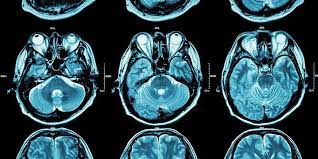

Area cedera serta letak dari cedera ini juga bervariatif, tergantung dari penyebab dari cedera. Namun ukuran saraf yang sangat kecil membuat Diffuse Axonal Injury menjadi sulit untuk terdeteksi bahkan setelah menggunakan pemeriksaan pencitraan seperti CT Scan dan sinar-X. Namun saat terduga mengalami Diffuse Axonal Injury, dokter biasanya akan langsung memulai tindakan penanganan segera.